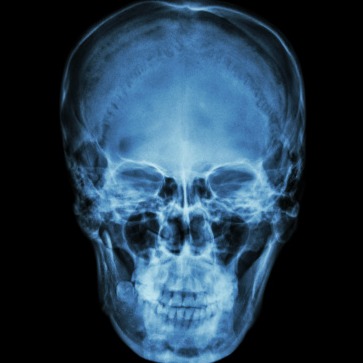

La cefalometria è una tecnica utilizzata in ortodonzia e chirurgia maxillo-facciale per valutare la posizione e le dimensioni delle ossa e dei tessuti molli del cranio e del viso. Questo metodo si basa sull’analisi di radiografie speciali chiamate tele-radiografie laterali della testa, che mostrano la struttura scheletrica del volto e del cranio.

La diagnosi basata sulla cefalometria prevede le misurazioni delle proporzioni delle strutture cranio-facciali, ottenute da radiografie speciali chiamate tele-radiografie laterali della testa. I passaggi principali previsti da una diagnosi con cefalometria sono:

• acquisizione dell’immagine: innanzitutto, viene eseguita la tele-radiografia laterale della testa utilizzando apparecchiature radiografiche speciali. Questa radiografia fornisce un’immagine bidimensionale della testa e del collo, mostrando le strutture scheletriche e dentali;

• misurazioni delle strutture cranio-facciali: sulla radiografia laterale della testa, vengono effettuate diverse misurazioni di riferimento utilizzando punti anatomici specifici sul cranio e sulle strutture facciali. Queste misurazioni includono angoli, distanze lineare e rapporti tra le diverse strutture;